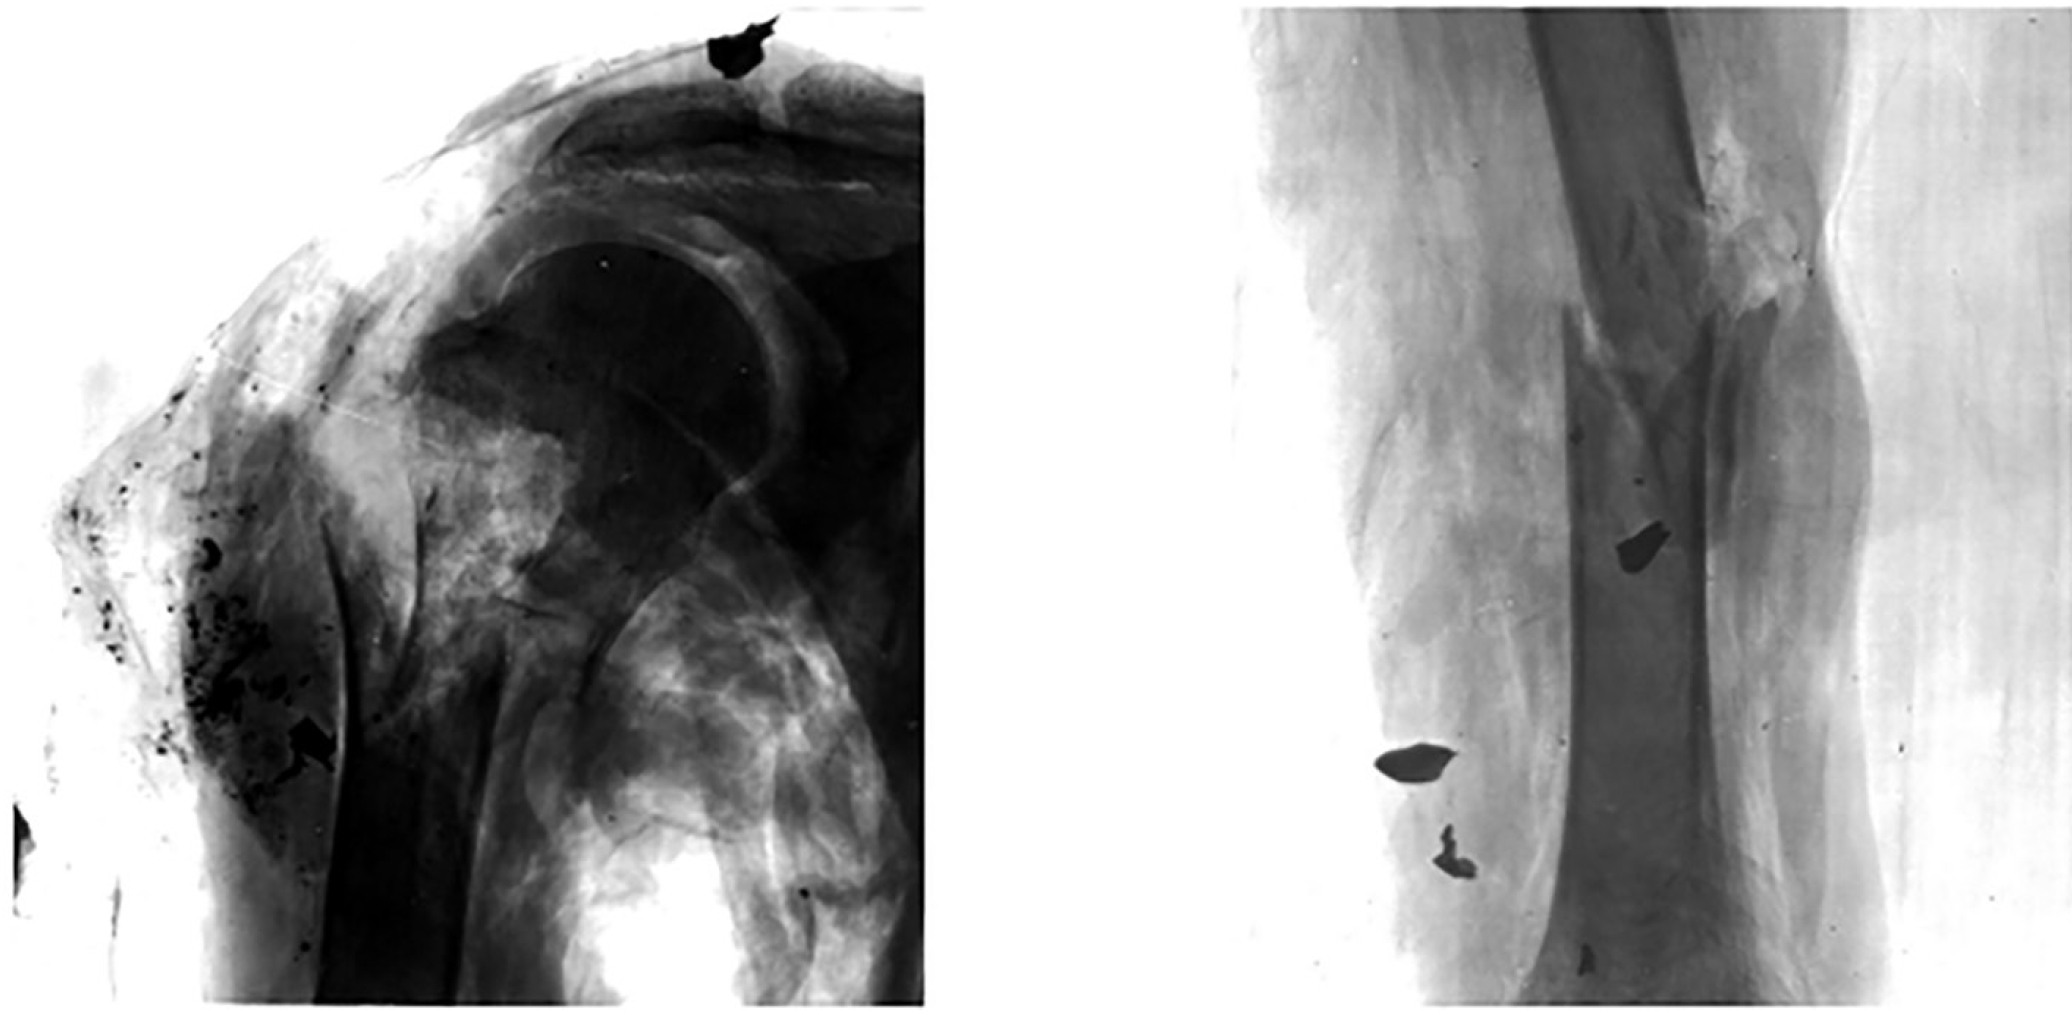

Разлёт рикошетирующих элементов пуль, как правило, происходит при углах подлета пули к бронезащите 20 и более градусов относительно направления стрельбы, и угол их разлёта в незначительной степени зависит от применяемого оружия. От рикошетировавших фрагментов пуль могут наблюдаться переломы плечевых костей (рис. 6), повреждения мягких тканей затылочной области, шеи, нижней челюсти, предплечья, кисти и бедра [10, 12].

Рис. 6. Повреждения верхних конечностей при наружном рикошете: а – огнестрельный перелом шейки правой плечевой кости; б – огнестрельный перелом диафиза левой плечевой кости при наружном рикошете